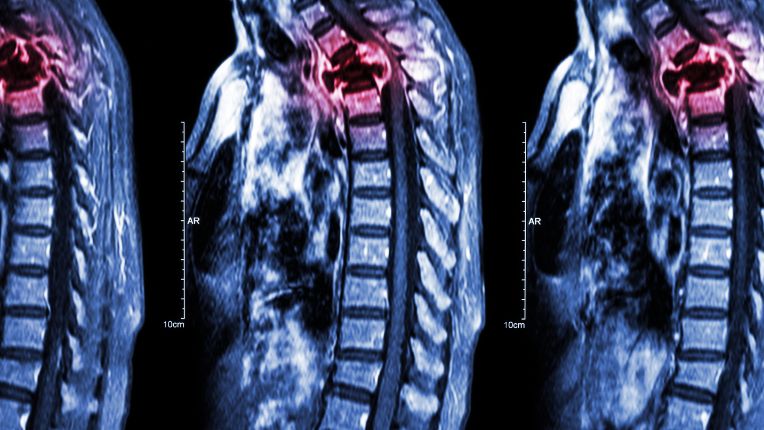

Métastases foie, cerveau, poumon, osseuses

Le diagnostic peut mettre en évidence l'apparition de métastases cérébrales, hépatiques (foie), pulmonaires, osseuses...